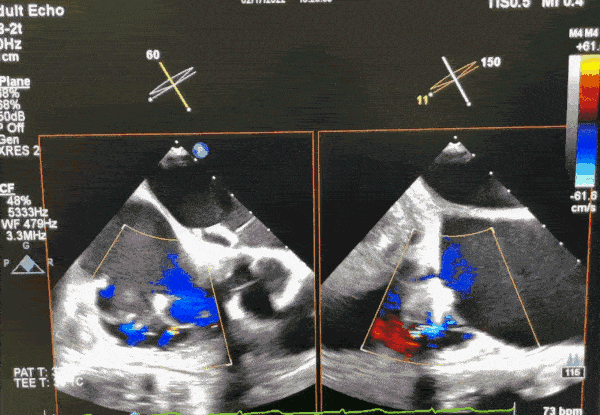

手术在经食道超声心动图和DSA引导下进行,武汉协和医院董念国教授团队使用NeoBlazar™经导管三尖瓣夹合器,经股静脉穿刺,送入导丝建立右心房通路,送入三尖瓣夹合器械,在右心房调整双层控弯导管,将第一枚夹合器置于三尖瓣前叶与隔叶间反流最大区域,在DSA与超声双重指引下跨瓣进行瓣叶的捕获与夹合,在经食道超声心动图反复确认手术效果后,释放三尖瓣瓣膜夹;第二枚夹合器顺利送至后隔交界,捕捉三尖瓣后叶和隔叶,确认瓣叶夹持稳固后释放夹合器。此次术中共植入2枚瓣膜夹,瓣膜夹位置和功能良好,术后即刻超声心动图评估三尖瓣反流降至轻度,手术取得圆满成功。

术中超声